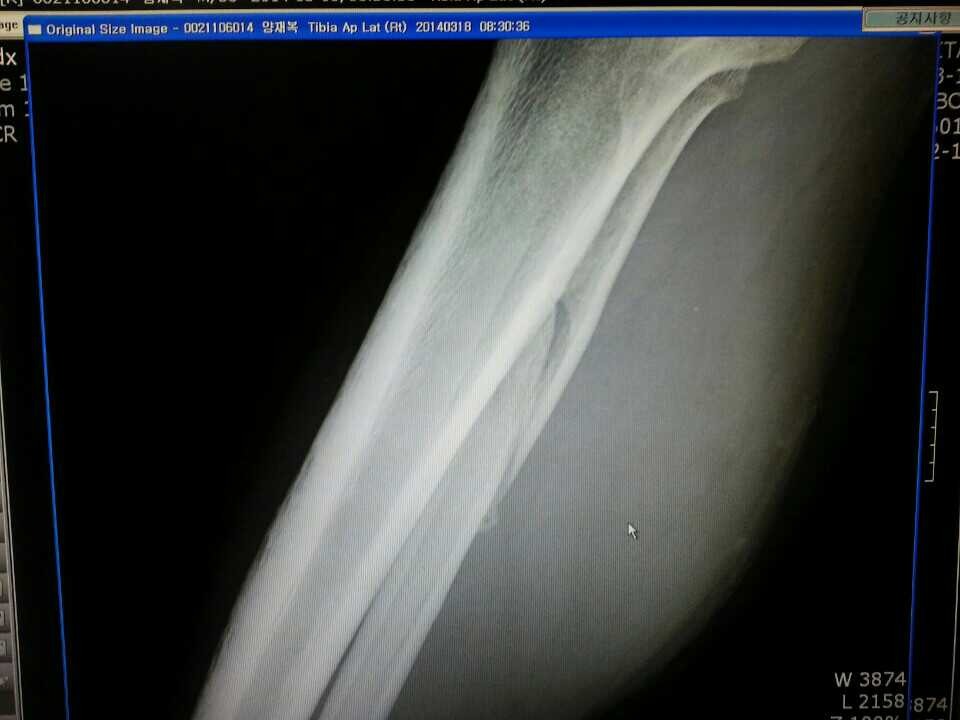

또한 비골도 같은사고로 골절되었었는데요 지금 좀 붙어가는것같은데 이렇게 대충 붙어도 상관없나요?